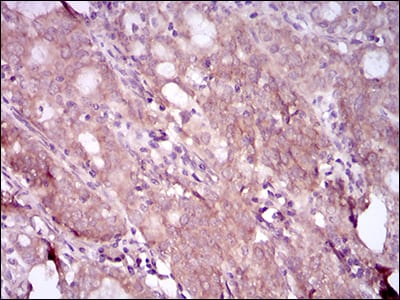

分类: 科研抗体货号: 30505别名: CD146; MUC18应用: WB,IHC,FCM反应种属: Human